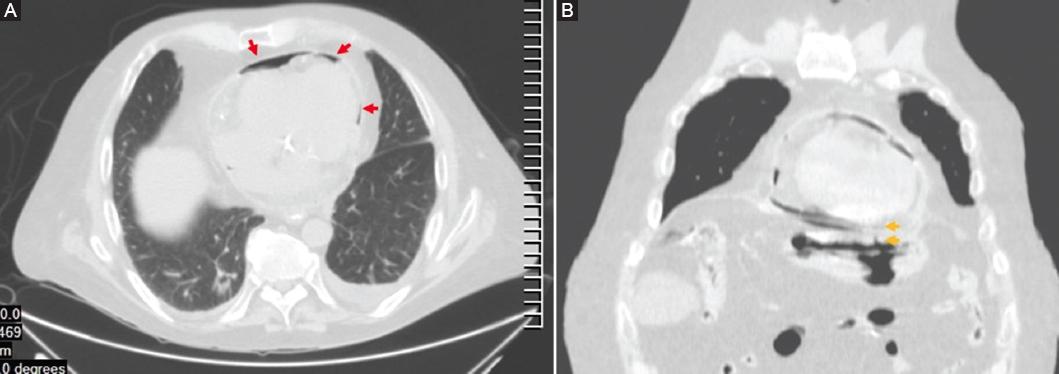

Dentro de los estudios de gabinete, la radiografía de tórax mostró neumopericardio (Fig. 1) y la tomografía computarizada (TC) toracoabdominal una comunicación fistulosa en la curvatura menor al pericardio con presencia de neumopericadio, sin aire libre abdominal (Fig. 2). Decidimos realizar una endoscopia gastroduodenal, con hallazgo de una úlcera gástrica en el cuerpo anterior gástrico y penetración al mediastino, con visualización del movimiento cardiaco a través del pericardio, sin evidencia de sangrado activo (Fig. 3). Posteriormente se realizó un ecocardiograma, sin evidencias de compromiso del gasto cardiaco.

Figura 2 Tomografía computarizada toracoabdominal simple en ventana pulmonar. A: corte axial que muestra neumopericardio (flechas). B: corte coronal en el que se observa el trayecto fistuloso que comunica la cámara gástrica con el pericardio (flechas).